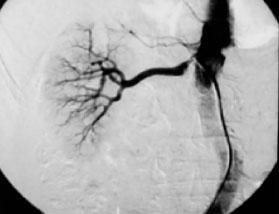

4.肾动脉造影 是目前公认的诊断肾动脉狭窄的金标准(图5—5),能准确显示肾动脉狭窄部位、范围、程度及侧支循环形成情况,还可观察肾动脉狭窄远端逆行性充盈及侧支循环并可同时进行介入治疗,结合测定两侧肾静脉血浆肾素活性判断手术疗效。肾功能不全患者宜选用非离子化造影剂,并用数字减影血管造影术(DSA),以减少造影剂用量,减轻造影剂对肾的损害。肾动脉造影是一种有创性检查,并可引起造影剂肾病和胆固醇栓塞,因此不作为常规筛选性检查。

图5—5 右肾动脉狭窄(肾动脉造影)

其应用指征为:①肾动脉狭窄介入或手术治疗前的必要准备,明确狭窄部位、程度、范围、侧支循环及伴随的其他病理情况;②临床上诊断肾血管性高血压、缺血性肾脏病、冠心病心绞痛等,经非侵入性检查提示一侧肾动脉狭窄大于50%,或有明显的血流动力学改变,或30岁以前及50岁以后出现高血压,不对称肾脏缩小,用血管紧张素转换酶抑制剂后肾功损伤。建议对可疑肾动脉狭窄的高危患者在冠状动脉造影的同时进行肾动脉造影。